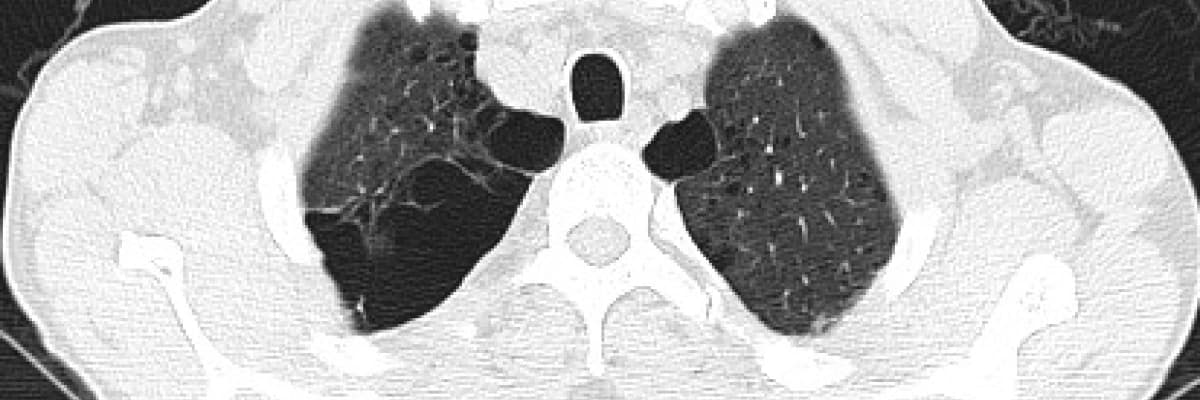

Yaşlanmayla ve çeşitli sebeplerle bronşların elastikiyeti azalır, ödem oluşur ve daralma başlar. Bu duruma kronik tıkayıcı akciğer hastalıkları (KOAH) adı verilir. Havanın içeri girişinde değil dışarı çıkmasında problem başlar. Böylelikle içerideki hava hapsolarak dışarı atılamaz ve nispeten sağlam akciğer dokusu da baskılanmış olur. İşte bronşçuklardan sonraki hava boşluklarının anormal kalıcı genişlemesi durumuna Amfizem denilmektedir.

Tedavi: Amfizemin tek bir tedavisi yoktur. Akciğer dokusunda meydana gelen tahribatı düzeltmek mümkün olmadığı için, esas önemli olan hastalığın erken tanınması, sigara ve diğer etkenlerden uzaklaşılmasıdır. Bronş genişletici ilaçlar hastalığın ilerlemesini yavaşlatır. Tahrip olan ve genişleyen akciğer dokusu, alttaki nispeten sağlam dokuyu da baskılamaktadır.

Amfizemde cerrahi tedavi: Amaç boşuna genişlemiş işlevsiz dokuları çeşitli yöntemlerle çıkararak alttaki sağlam akciğer dokusunun ve diyafram hareketlerinin rahatlamasını sağlamaktır. Cerrahi tedavi seçenekleri, varsa hava kistlerinin çıkarılması, akciğer hacim küçültme ameliyatları ve akciğer naklidir.

Akciğer hacim küçültme ameliyatı; 1950'li yıllardan beri yapılmaktadır. Cerrahi tedavide amaç; akciğerdeki aşırı havalanmayı azaltmak amacıyla hasarlı bölgelerinin çıkartılmasıdır. İşe yaramayan akciğer hacminin azaltılmasıyla hava hapsi azalır, elastikiyet artar, hava çıkış hızı artar, göğüs kafesi ve diyaframın daha etkin bir biçimde iş görmesi sağlanır. Tüm bunlara bağlı olarak nefes darlığı azalır, egzersiz kapasitesi artar ve yaşam kalitesinde düzelme elde edilir.

Hafızalı metalden (nitinol) üretilen akıllı sarmal teknolojisi günümüzde ön plana çıkmıştır. Tüm Avrupa ve ABD’de yıllardır uygulanmaktadır. Üst lob ağırlıklı olan, yaygın amfizem tiplerinde uygulanır. Hava kistlerin ön planda olduğu, sarmalı tutacak yeterli akciğer dokusunun olmadığı hastalar bu tedavi için uygun değildir.